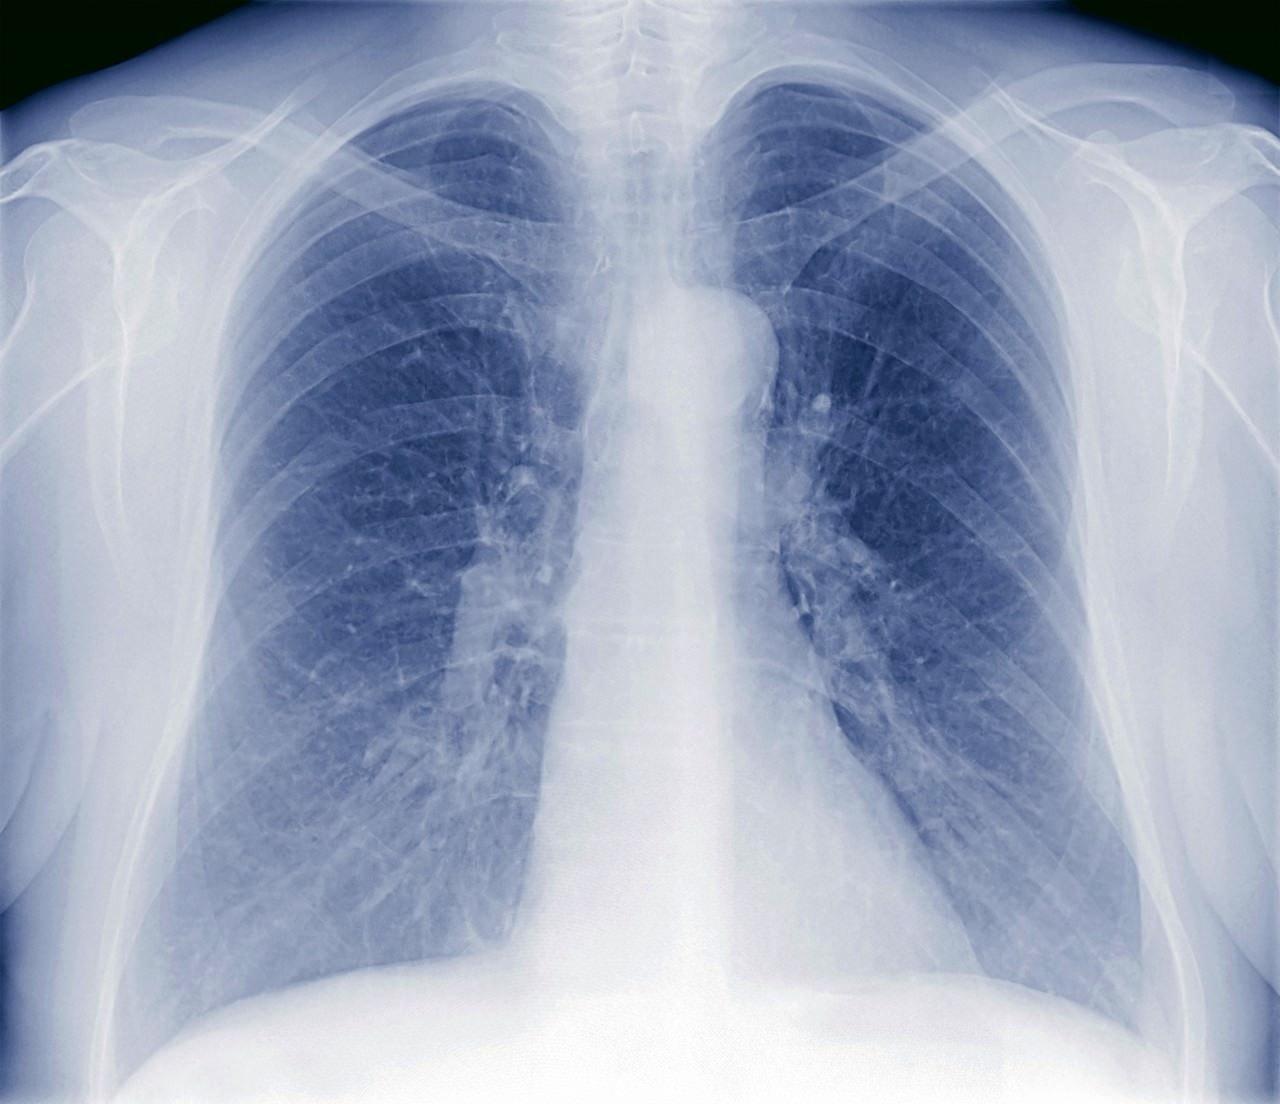

胸片能看出肺结核,但需结合其他检查综合判断胸片是检查肺结核的常见且重要手段,其原理是利用X射线的穿透性对胸部进行成像,通过观察肺部结构变化判断是否存在病变胸片能够显示肺结核的典型病灶,如阴影结节或空洞等异常征象例如,原发性肺结核可能表现为肺门淋巴结肿大,继发性肺结核则常见上叶尖后段或下叶背段的斑片状阴影,慢性纤维空洞。

拍片可以帮助诊断肺结核,但并非绝对准确拍片是诊断肺结核的重要手段拍片,尤其是胸部X线片和胸部CT,在肺结核诊断中发挥着关键作用在胸片上,肺结核常呈现出典型的影像学表现,如肺部的斑片状阴影结节影以及空洞形成等这些特征性的影像为医生提供了初步判断肺结核的重要依据胸部CT在诊断中更具。

拍胸片可以发现肺结核的局部病灶,但不能单独作为确诊依据具体分析如下胸片的作用胸片X线胸片是肺结核筛查的常用影像学检查手段,能够显示肺部是否存在异常阴影空洞纤维化或钙化等特征性病变典型的肺结核病灶在胸片上可能表现为上叶尖后段或下叶背段的浸润性阴影空洞形成或播散性病灶。

初步判断X线胸片可以对大部分的肺结核做出初步判断如果出现咳嗽咳痰咯血盗汗消瘦乏力等呼吸系统症状,X线胸片可以帮助医生初步判断是否存在肺结核的可能发现病灶X线胸片能够早期发现肺结核病灶,这对于肺结核的诊断具有重要意义辅助诊断虽然X线胸片可以做出初步判断,但诊断肺结核的金标准是。